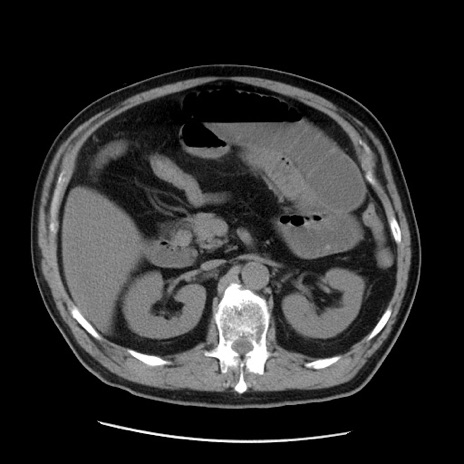

症例20(横断像)

【症例】 60歳代男性

【主訴】 腹部膨満、嘔吐

【現病歴】5日前頃より倦怠感を認め食事量減少し4日前の朝嘔吐、食事摂取困難となった。 3日前近医受診し点滴施行され整腸剤などを処方された。 当日他院を受診し、腹部膨満著明、炎症反応の上昇(CRP10.8、WBC11200)あり、紹介受診となる。

【身体所見】 意識JCS1 受け答えがはっきりしないBP 111/57mHg、 P 67bpm、、BT35.2°C、SpO2 97%(RA)、 腹部:膨隆、打診で鼓音あり、全体的に圧痛有り、腸蠕動音(-)、反跳痛ははっきりせず。

【データ】WBC 11400、CRP 14.20